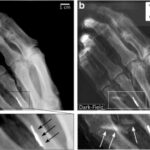

Use of the Hourglass peripheral embolisation device

This article evaluates a novel intravascular plug, the Hourglass peripheral embolisation device (PED). The use of this device is described, and its potential applications are discussed. In this study, the indications, success rate, and the procedure-related...